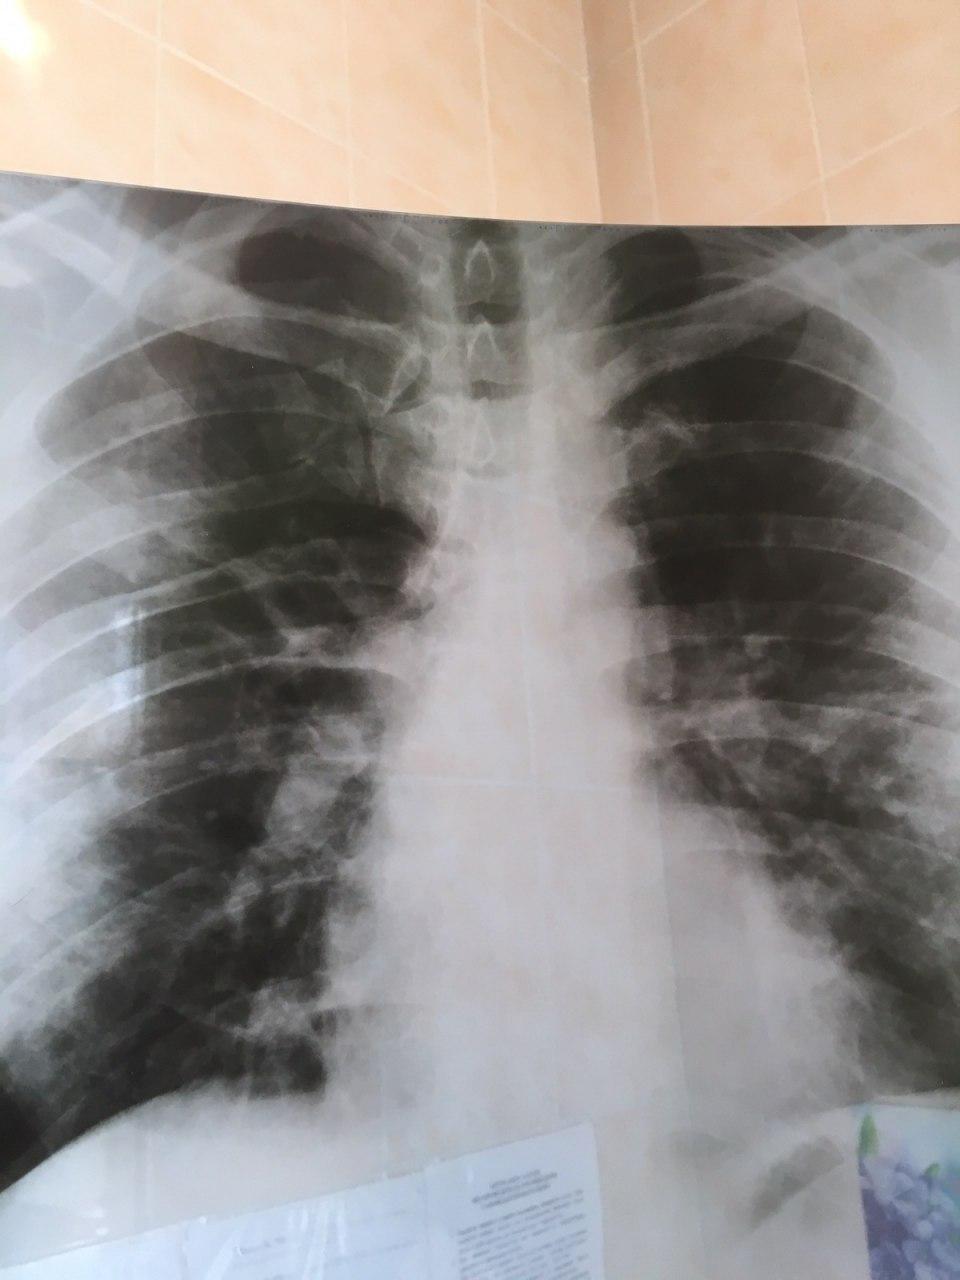

Будни врачей, которые борются с COVID-19 Facebook Яны Свердлюк